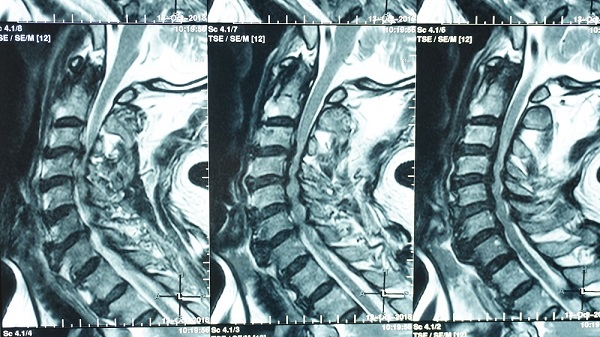

Ngày 15/10/2018, bệnh nhân Luật sư Tiến sỹ P.Đ.T, sinh năm 1946, ngụ ở TPHCM nhập viện trong tình trạng yếu tứ chi nặng diễn tiến nhanh. Bệnh nhân không thể tự đi lại được do mất khả dụng cơ tứ chi kèm tê nhiều và vụng về cử động đôi bàn tay. Thăm khám lâm sàng bệnh nhân có giảm nhiều sức cơ tứ chi, kèm hội chứng tháp, tăng phản xạ chi dưới. MRI cột sống cổ có chèn ép tủy nặng do hẹp trầm trọng ống sống cổ C3-C4, C4-C5, C5-C6. Theo nhận định của Ts.Bs.Huỳnh Hồng Châu, Trưởng khoa Ngoại thần kinh Bệnh viện Quốc tế City thì bệnh nhân nên được phẫu thuật giải áp tủy sống cổ sớm nhất có thể nhằm tránh rủi ro có thể diễn tiến đến tình trạng liệt tứ chi và ngưng thở do tổn thương tủy cổ trên C5 nếu như tình cờ xảy ra một sang chấn nhẹ vùng cổ.

Hình phim MRI cột sống cổ của bệnh nhân P.Đ.T.